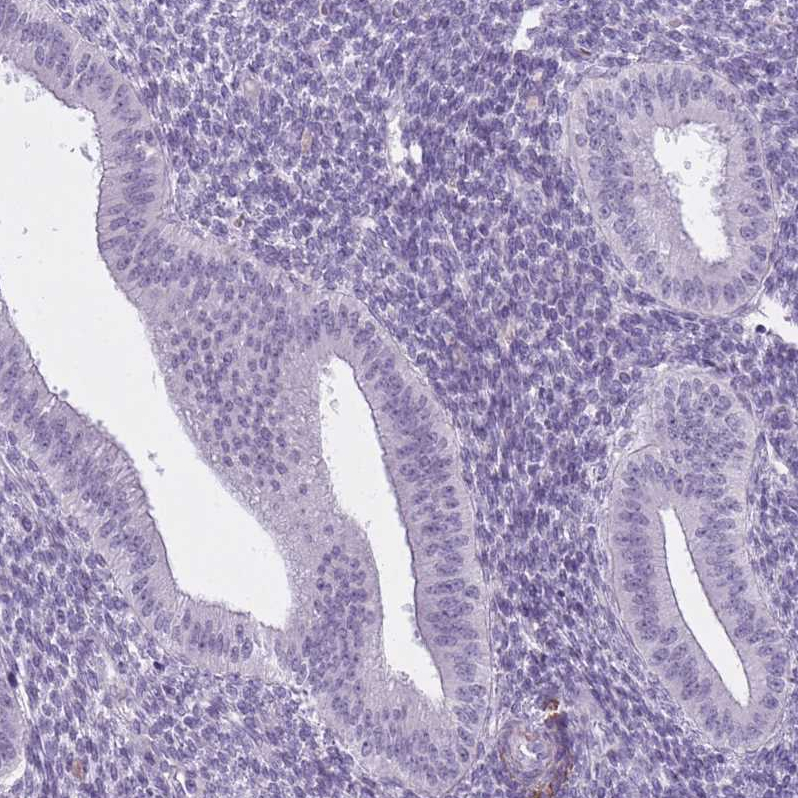

Immunohistochemistry analysis in human testis and endometrium tissues using HPA050527 antibody. Corresponding RFX4 RNA-seq data are presented for the same tissues.